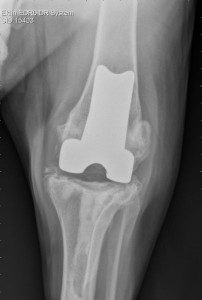

The commercial system consists of a polyethylene (plastic) component that is fixed to the tibia and a metal component that is fixed to the femur. The two components articulate with each other, creating a new weight-bearing surface and mimicking the movement of a normal joint during knee motion. The commercial total knee replacement system is suitable for dogs >15kg body weight. It is, however, reliant on the stabilising ligaments of the knee joint, known as the collateral ligaments – on the outside and inside of the knee – being intact for your dog to be suitable for a commercial total knee replacement; the cruciate ligaments do not need to be.

During surgery, the stifle joint (knee) is exposed through an incision on the side of the knee. The joint surfaces of both the femur and tibia are removed and replaced by two components. In the commercial system, a metal component is used to replace the damaged joint surface of the femur and an ultra-high molecular weight polyethylene (UHMWPE, plastic) implant is used to replace the damaged joint surface of the tibia; both components are fixed using orthopaedic cement. As the success of the commercial surgical system relies on the supporting ligaments of the knee, these ligaments are thoroughly checked prior to completion of the surgery.